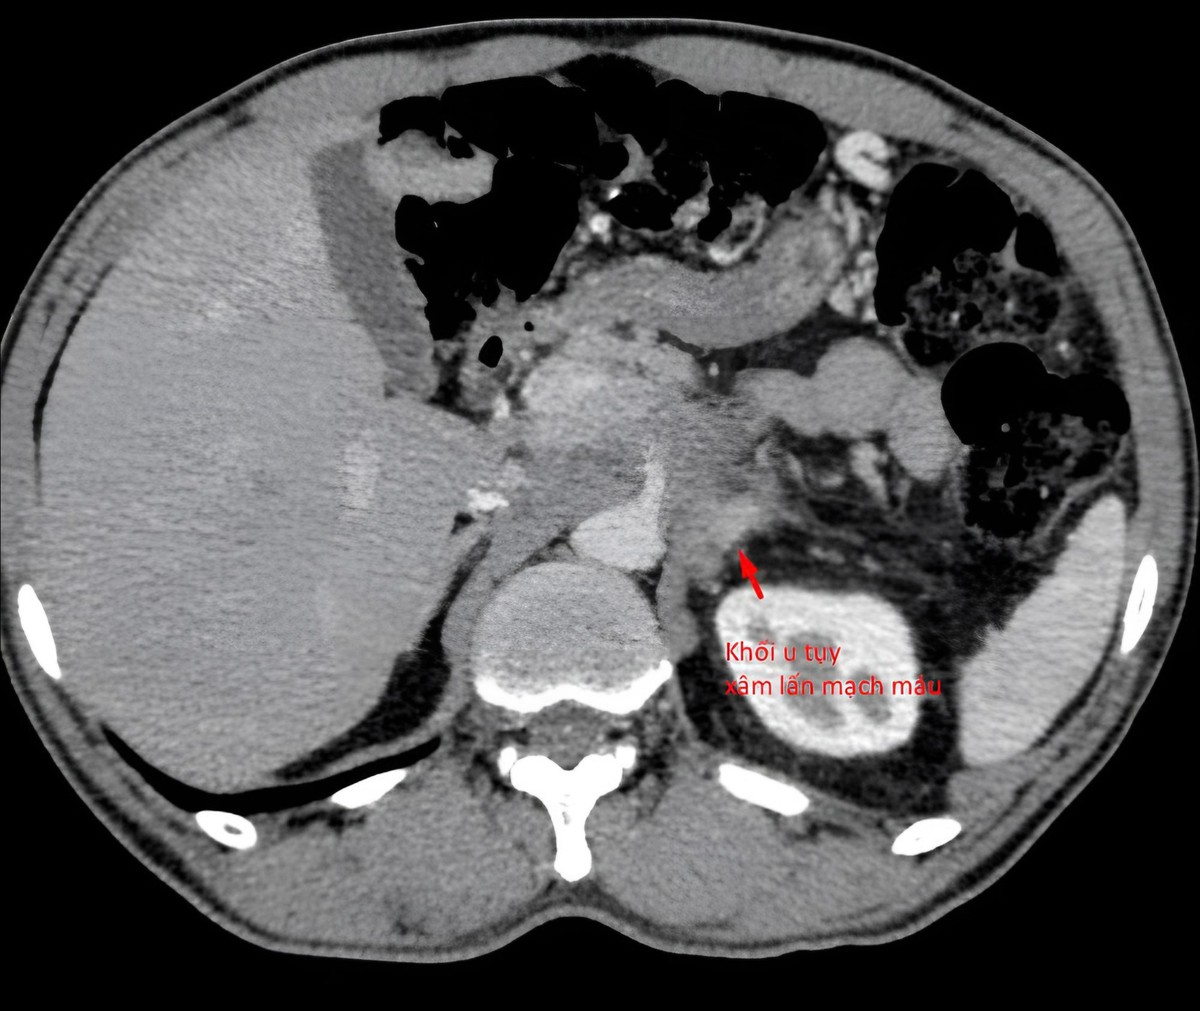

Bệnh nhân 64 tuổi được phát hiện có khối u tụy xâm lấn mạch máu

Khối u tụy xâm lấn thành mạch máu của bệnh nhân.

Bệnh nhân 64 tuổi được phát hiện có khối u tụy xâm lấn mạch máu. Khi chưa có kết quả sinh thiết, bệnh nhân gần như không thể tiếp cận các phác đồ điều trị chuẩn mực.

Khi được chuyển đến Trung tâm Chẩn đoán hình ảnh và Điện quang can thiệp Phương Đông, và qua phân tích chi tiết hình ảnh chụp cắt lớp và cộng hưởng từ, ê-kíp chuyên môn nhận định rằng tất cả các hướng tiếp cận sinh thiết thường quy đều không khả thi do nguy cơ tổn thương mạch máu lớn và các cơ quan lân cận.

Trong quá trình hội chẩn, các bác sĩ xác định chỉ còn duy nhất một "khe cửa hẹp" để tiếp cận khối u: từ phía sau, xuyên qua khoảng giữa cột sống và thận. Đây là đường vào rất khó, đòi hỏi kỹ thuật can thiệp tinh vi, độ chính xác cao và tiềm ẩn nhiều rủi ro nếu không được kiểm soát chặt chẽ.